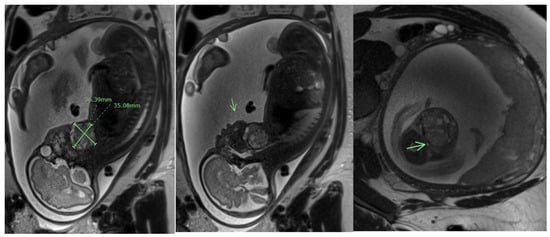

- Danzer, E.; Hubbard, A.M.; Hedrick, H.L.; Johnson, M.P.; Wilson, R.D.; Howell, L.J.; Flake, A.W.; Adzick, N.S. Diagnosis and characterization of fetal sacrococcygeal teratoma with prenatal MRI. AJR Am. J. Roentgenol. 2006, 187, W350–W356. [Google Scholar] [CrossRef]

- Okamura, M.; Kurauchi, O.; Itakura, A.; Naganawa, S.; Watanabe, Y.; Mizutani, S. Fetal sacrococcygeal teratoma visualized by ultra-fast T2 weighted magnetic resonance imaging. Int. J. Gynecol. Obstet. 1999, 65, 191–193. [Google Scholar] [CrossRef] [PubMed]

- Chen, C.P.; Shih, J.C.; Huang, J.K.; Wang, W.; Tzen, C.Y. Second-trimester evaluation of fetal sacrococcygeal teratoma using three-dimensional color doppler ultrasound and magnetic resonance imaging. Prenat. Diagn. 2003, 23, 602–603. [Google Scholar] [CrossRef] [PubMed]

- Tosun, M.; Çam, I.; Uslu, H.; Doğan, Y.; Anik, Y. A single-center experience of magnetic resonance imaging findings of fetal sacrococcygeal teratomas. Turk. J. Med. Sci. 2022, 52, 1190–1196. [Google Scholar] [CrossRef] [PubMed]

- Kirkinen, P.; Partanen, K.; Merikanto, J.; Ryynänen, M.; Haring, P.; Heinonen, K. Ultrasonic and magnetic resonance imaging of fetal sacrococcygeal teratoma. Acta Obstet. Gynecol. Scand. 1997, 76, 917–922. [Google Scholar] [CrossRef] [PubMed]

- Ulm, B.; Muin, D.; Scharrer, A.; Prayer, D.; Dovjak, G.; Kasprian, G. Prenatal ultrasound and magnetic resonance evaluation and fetal outcome in high-risk fetal tumors: A retrospective single-center cohort study over 20 years. Acta Obstet. Gynecol. Scand. 2020, 99, 1534–1545. [Google Scholar] [CrossRef]